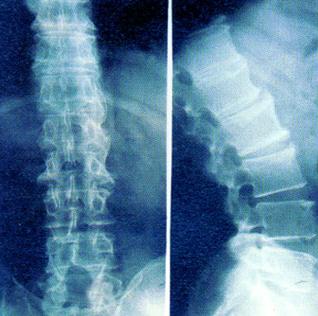

强直性脊柱炎主要以脊柱病变,累及骶髂关节,引起脊柱强直和纤维化,造成不同程度眼、肺、肌肉、骨骼病变,这给患者的身体带来了很多的伤害。所以需要在日常生活中做好预防强直性脊柱炎的工作,避免此病的侵害。那么,平时怎么去预防强直性脊柱炎?下面一起来看看医生是怎么说的。